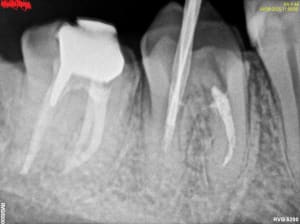

558904719_10163144646272247_6774572045327740986_n.jpg